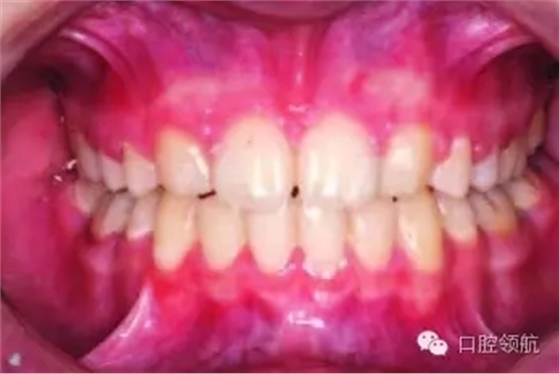

正畸治療結(jié)束后,尖牙是如何被改形的呢(圖3.7)?

使用復(fù)合樹脂材料在尖牙上堆塑出側(cè)切牙的近中尖。